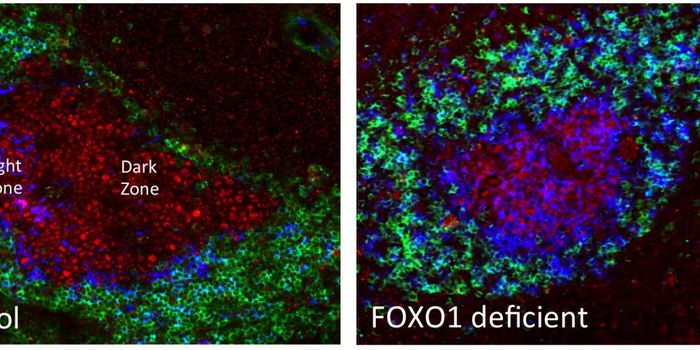

DEC 04, 2015ImmunologyThe germinal center of the immune system plays a complicated dual role in the body: vitally selecting B cells secreting ...